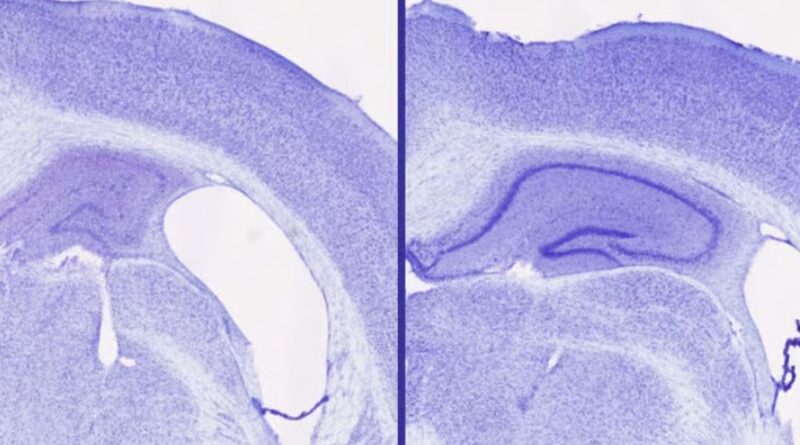

Crédito:Treatment with lemborexant (right) resulted in larger volume in the hippocampus (central purple spiral) and a smaller gap in brain tissue (white space) compared with another sleep aid treatment (left)Samira Parhizkar/WashU Medicine Um auxiliar de sono amplamente disponível demonstrou um potencial inesperado no apoio à saúde cerebral, reduzindo significativamente o acúmulo de proteínas tau —...